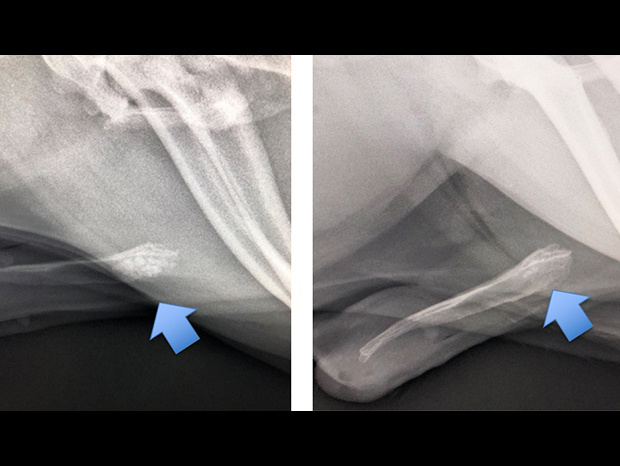

破砕前

破砕後

結石破砕を依頼された。左が破砕前、陰茎骨に結石が詰まっている。

右は破砕後。破砕が可能だったので尿道切開をせずに2時間後に帰宅した。